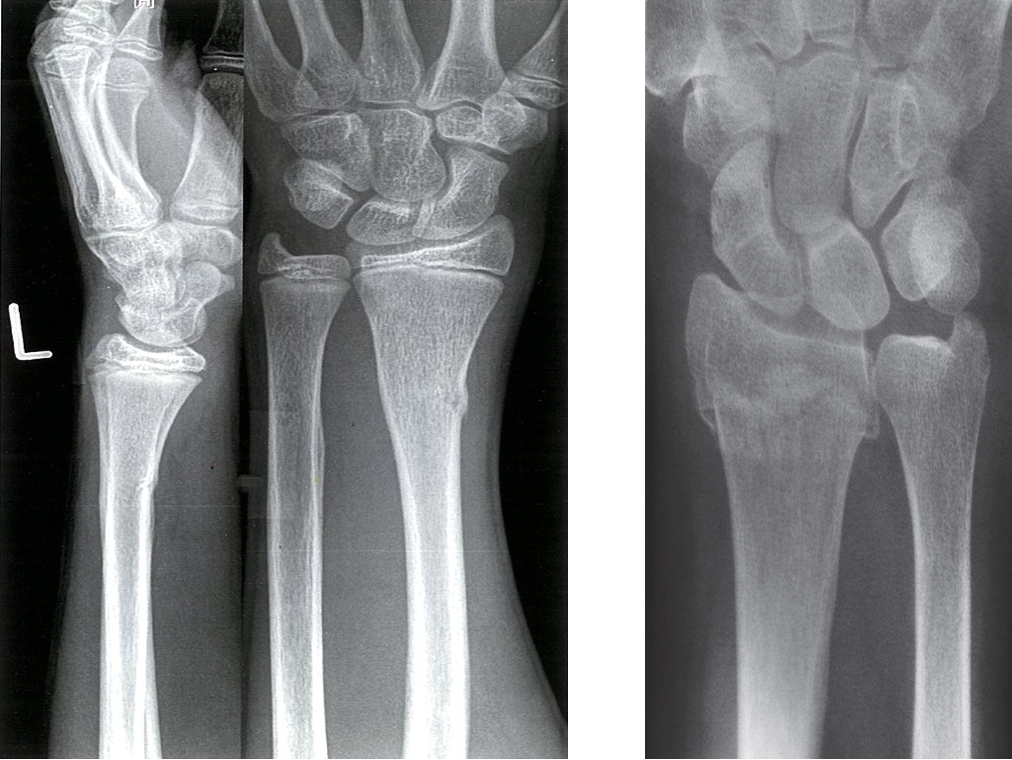

A. X-ray distal left forearm (left: lateral view; right: PA view) of an adolescent - A Greenstick fracture of the distal radius is seen. The cortex on the radial (lateral) side of the fracture is disrupted and buckled . However, the fracture line has not traversed the bone. The ulnar (medial) side of the radius is bowed, but the cortex is intact

B. Step in cortex and interruption of bony trabeculae (arrow) in a Colles’ fracture usually found in elderly